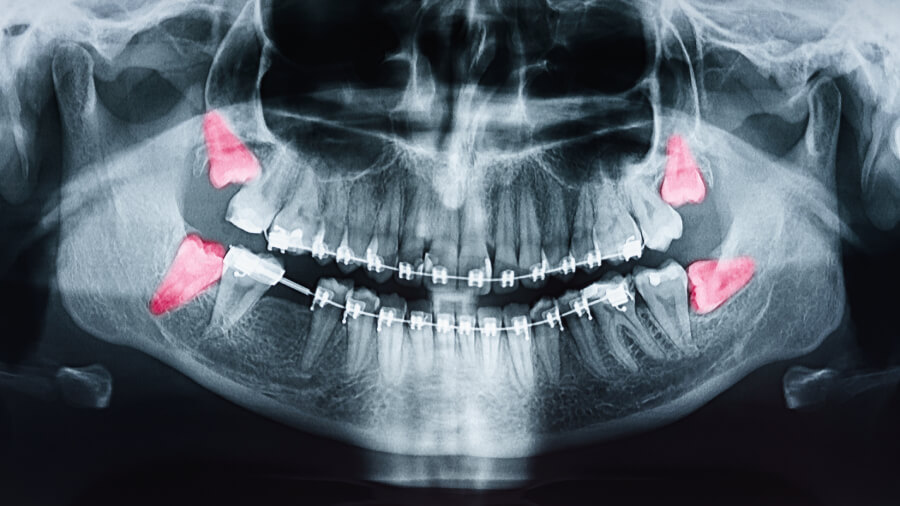

Wisdom Teeth Removal

Do I Have To Have My Wisdom Teeth Removed?

Dangers Of Leaving Wisdom Teeth Alone